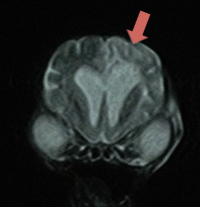

• 脳炎

発作などを引き起こす代表的な脳の病気です。要因は様々で、MRI検査に加え脳脊髄液検査を併用して総合的に診断します。

脳炎を疑う症例